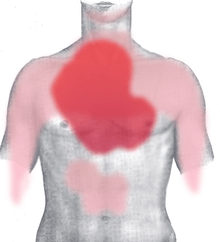

Myocardial infarction (MI) or acute myocardial infarction (AMI), commonly known as a heart attack, occurs when blood flow stops to a part of the heart causing damage to the heart muscle. The most common symptom is chest pain or discomfort which may travel into the shoulder, arm, back, neck, or jaw. Often it is in the center or left side of the chest and lasts for more than a few minutes. The discomfort may occasionally feel like heartburn. Other symptoms may include shortness of breath, nausea, feeling faint, a cold sweat, or feeling tired.[1] About 30% of people have atypical symptoms,[2] with women more likely than men to present atypically.[3] Among those over 75 years old, about 5% have had an MI with little or no history of symptoms.[4] An MI may cause heart failure, an irregular heartbeat, or cardiac arrest.[5][6]

The onset of symptoms in myocardial infarction (MI) is usually gradual, over several minutes, and rarely instantaneous.[18] Chest pain is the most common symptom of acute MI and is often described as a sensation of tightness, pressure, or squeezing. Chest pain due to ischemia (a lack of blood and hence oxygen supply) of the heart muscle is termed angina pectoris. Pain radiates most often to the left arm, but may also radiate to the lower jaw, neck, right arm, back, and upper abdomen,[19] where it may mimic heartburn. Levine's sign, in which a person localizes the chest pain by clenching their fists over their sternum, has classically been thought to be predictive of cardiac chest pain, although a prospective observational study showed it had a poor positive predictive value.[20]

Atypical symptoms are more frequently reported by women, the elderly, and those with diabetes when compared to their male and younger counterparts.[23][24] Women also report more numerous symptoms compared with men (2.6 on average vs. 1.8 symptoms in men).[23] The most common symptoms of MI in women include dyspnea, weakness, and fatigue. Fatigue, sleep disturbances, and dyspnea have been reported as frequently occurring symptoms that may manifest as long as one month before the actual clinically manifested ischemic event. In women, chest pain may be less predictive of coronary ischemia than in men.[25] Women may also experience back or jaw pain during an episode.[26]